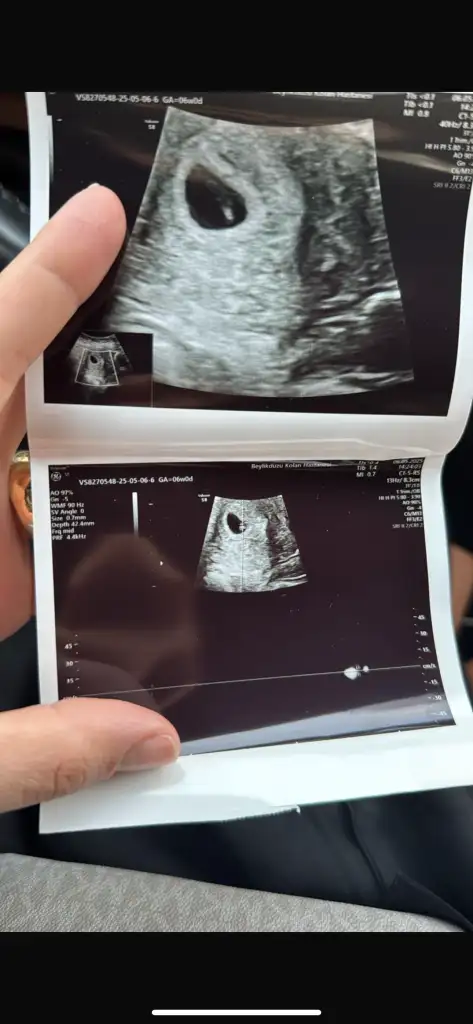

Kızlar 6-8 haftalık ultrason görüntülerinizi atın tahmin yapalım . Ya da cinsiyeti öğrenen annelerimiz 6-8 haftalık görüntülerini atsın bize de fikir olsun![]()

Erkek benceBanada bakarmısınız7+0 vajinal ultrason

Banada bakar mısınız? 6+3 vajinal ultrasonKız bebeğe benziyor

Merhaba 8+2 vajinal muayene sizce cinsiyeti nedirMerhaba 11+4 görüntüsü. Tahminlerinizi bekliyorum